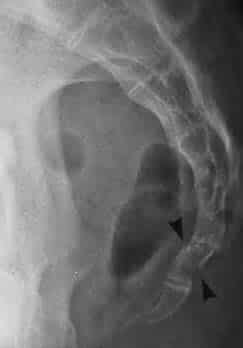

The coccyx (also known as the tailbone) is the terminal part of the vertebral column. It is comprised of four vertebrae, which fuse to produce a triangular shape. In this article, we will discuss the anatomy of the coccyx – its structure, bony landmarks, ligaments and clinical relevance. Pro Feature - 3D Model You've Discovered a Pro Feature Access our 3D Model Library Explore, cut, dissect, annotate and manipulate our 3D models to visualise anatomy in a dynamic, interactive way. Learn More Development and Structure The coccyx arises embryologically as the skeletal remnant of the caudal eminence that is present from weeks 4-8 of gestation. This eminence subsequently regresses, but the coccyx remains. Initially, the four coccygeal vertebrae are separate, but throughout life they fuse together to form one continuous bone. There is considerable variation in structure between individuals. One common variant is failure of the first coccygeal vertebra (Co1) to fuse, remaining separate throughout adult life. In some individuals, there can be one more or one less coccygeal vertebra, giving the individual a coccyx with 5 or 3 vertebrae respectively. Bony Landmarks The coccyx consists of an apex, base, anterior surface, posterior surface and two lateral surfaces. The base is located most superiorly, and contains a facet for articulation with the sacrum. The apex is situated inferiorly, at the terminus of the vertebral column. The lateral surfaces of the coccyx are marked by a small transverse process, which projects from Co1. The coccygeal cornua of Co1 are the largest of the small articular processes of the coccygeal vertebrae. They project upwards to articulate with the sacral cornua. By TeachMeSeries Ltd (2025) Fig 1Bony landmarks of the coccyx. Joints The coccyx articulates with the sacrum at a fibrocartilaginous joint called the sacrococcygeal symphysis. Movement here is limited to minor flexion and extension which occurs passively, for example during defecation and labour. Ligaments The sacrococcygeal symphysis is supported by five ligaments: Anterior sacrococcygeal ligament – a continuation of the anterior longitudinal ligament of the spine, and so connects the anterior aspects of the vertebral bodies. Deep posterior sacrococcygeal ligament – connects the posterior side of the 5th sacral body to the dorsal surface of the coccyx. Superficial posterior sacrococcygeal ligament – attaches the median sacral crest to the dorsal surface of the coccyx. Lateral sacrococcygeal ligaments – run from the lateral aspect of the sacrum to the transverse processes of Co1. Interarticular ligaments – stretch from the cornua of the sacrum to the cornua of the coccyx. Attachments One of the key functions of the coccyx is as an attachment point for various structures. The gluteus maximus attaches to the coccyx, as does the levator ani muscle, which is a key component of the pelvic floor. The anococcygeal raphe is a thin, fibrous ligament which runs from the coccyx and helps support the position of the anus. Clinical Relevance Fractured Coccyx An abrupt fall onto the buttocks, for example falling off a chair, can fracture the coccygeal vertebrae. This condition is normally managed with conservative care, although severe fractures may require in-patient treatment. By Nevit Dilmen (Own work) [CC BY-SA 3.0 ], via Wikimedia Commons Fig 2Radiograph of a fractured coccyx (demonstrated by the arrows). Coccydynia Coccydynia refers to a sensation of general discomfort around the coccyx, and has a wide range of causes. Childbirth may be a cause, as the stretching of pelvic floor muscles during labour puts pressure on their attachment to the coccyx, causing pain. Blunt trauma can contribute, as can poor posture when cycling or rowing, leading to irritation of the bone. Normally coccydynia is an acute condition, although if the pain lasts for more than 3 months it is considered chronic, and requires more specialised treatment. Sacrococcygeal Teratoma A sacrococcygeal teratoma is a tumour of the coccyx that is thought to derive from the embryological primitive streak. Mostly they are benign, although 12% of the time they are malignant and life-threatening. They are present in 1/35,000 live births, and so are the most common presenting tumour in newborns. Do you think you’re ready? Take the quiz below Pro Feature - Quiz The Coccyx Question 1 of 3 Submitting... Skip Next Rate question: You scored 0% Skipped: 0/3 1800 More Questions Available Upgrade to TeachMeAnatomy Pro Challenge yourself with over 1800 multiple-choice questions to reinforce learning Learn More Rate This Article